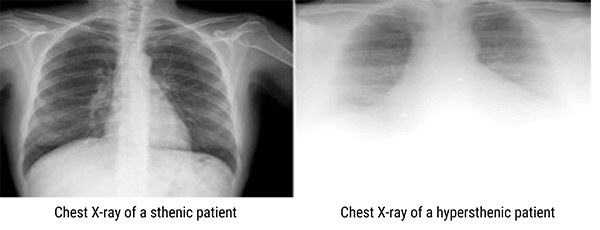

On the other hand, the radiographer has to increase these technical factors for hypersthenic patients and to decrease them for asthenic patients to improve the image quality. Let’s see the difference in the image clarity below.

This image shows a chest X-ray of a sthenic and hypersthenic patients.

As you can see, the image on the right needs a large adjustment of technical factors to produce an image of optimal density. However, the image on the left shows X-ray penetration of the abdominal cavity below the diaphragm with clearly visible lower ribs and spinal structures.

Please keep in mind that on some hypersthenic patients, an image of optical density may not be achievable.